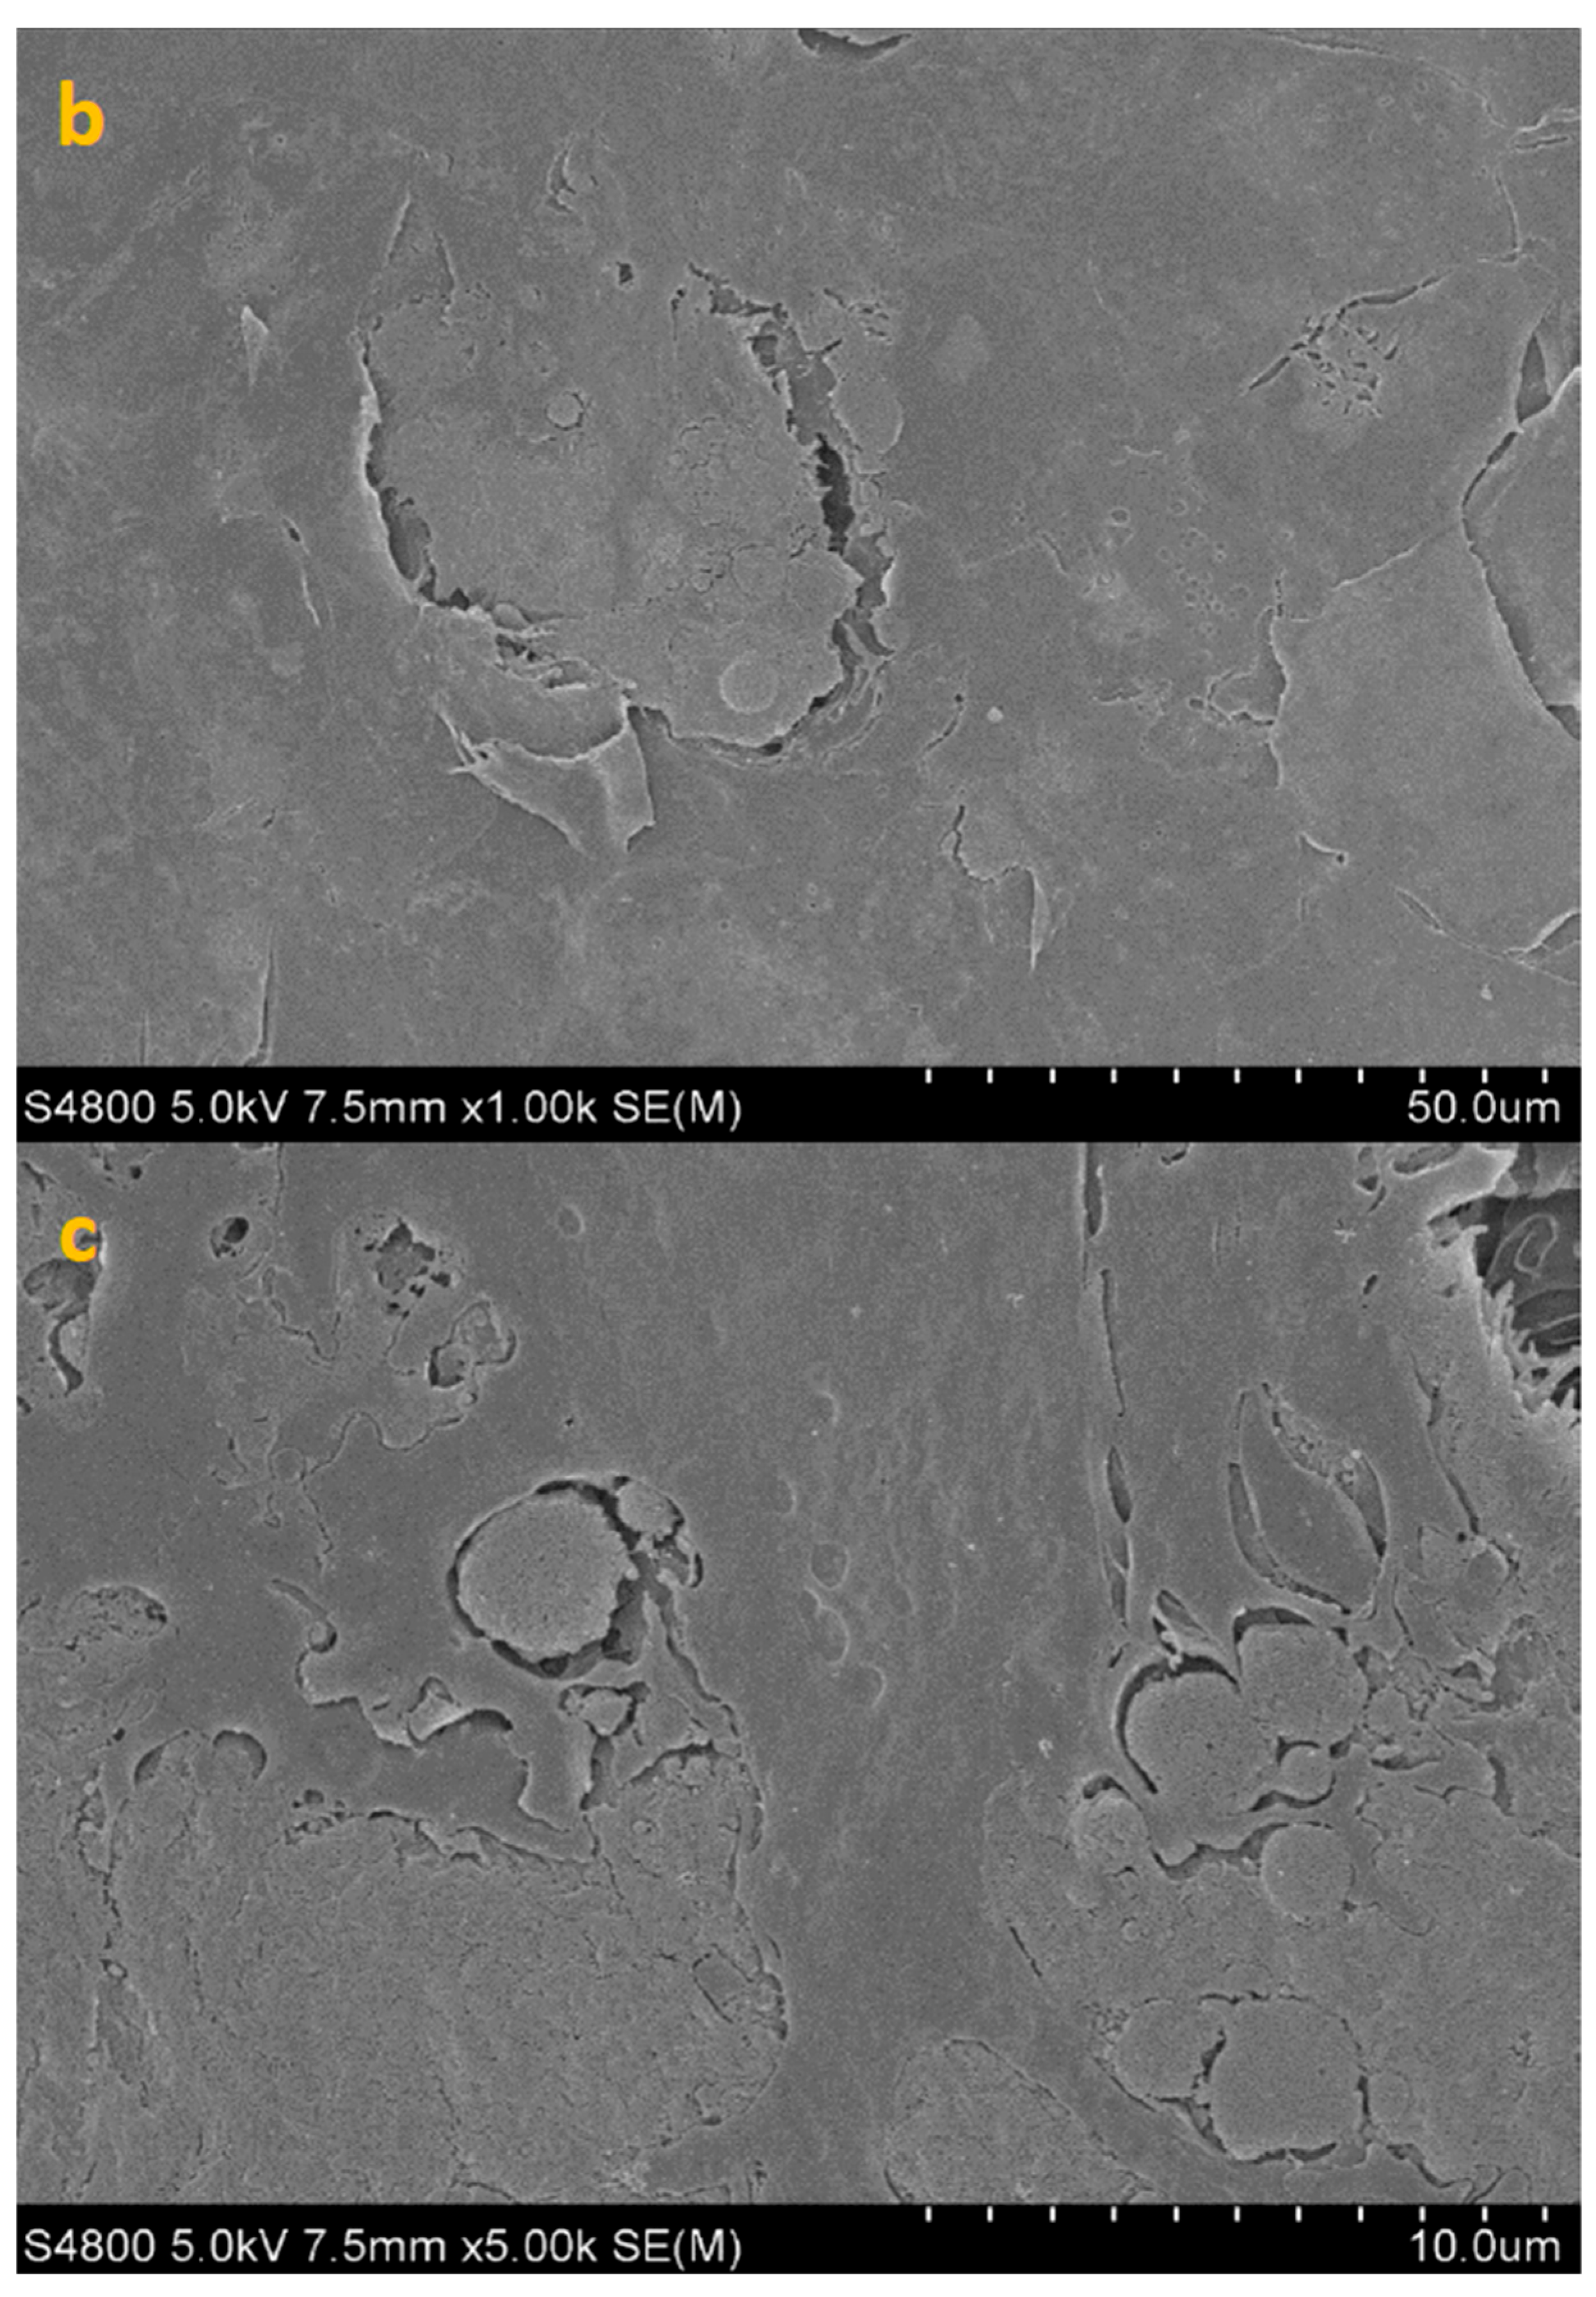

- The positive control group (HCE + AC) was designed to reproduce the natural course of infection. In this condition, HCE tissues were inoculated with A. castellanii trophozoites (10 µL suspension at 5 × 106 cells/mL) and incubated for 24 h at 37 °C, 5% CO2. This group provided the reference standard for maximal amoebic adhesion in the absence of any treatment.

- The first study group (HCE + TP + AC, co-incubation paradigm) was intended to simulate a prophylactic scenario, in which CORNEIAL MED was present on the ocular surface at the time of amoebic challenge. A volume of 20 µL of CORNEIAL MED was applied to the apical surface of the epithelium, immediately followed by 10 µL of A. castellanii suspension. The tissues were then incubated for 24 h under standard conditions. This setup assessed the capacity of the product to interfere with the initial steps of trophozoite adhesion and colonization.

- The second study group (HCE + AC + TP, post-adhesion paradigm) was designed to mimic an early therapeutic intervention, corresponding to the clinical situation in which amoebae have already established initial contact with the corneal epithelium. In this protocol, HCE tissues were first inoculated with A. castellanii suspension and maintained for 3 h to allow adhesion. After this period, 20 µL of CORNEIAL MED was applied to the surface, and the tissues were incubated for an additional 24 h. This group enabled the evaluation of the inhibitory effect of the product once adhesion had already occurred.